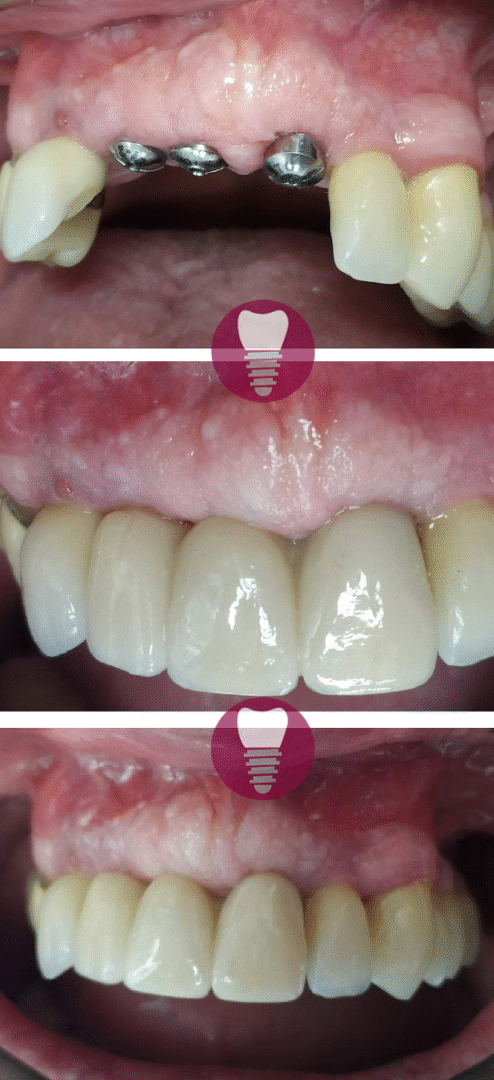

Este caso clínico muestra un tratamiento de restauración completa de la dentadura superior. Este tipo de intervención es ideal para pacientes que presentan una pérdida significativa de piezas dentales en la arcada superior o que tienen dientes gravemente dañados debido a caries avanzadas, desgaste, o problemas periodontales.

En este tratamiento, se emplea una prótesis sobre barra en implantes, proporcionando una solución estable y estética que permite recuperar la funcionalidad y la apariencia de la sonrisa. Este enfoque no solo mejora la capacidad de masticación del paciente, sino que también refuerza la estructura facial y restaura la confianza en su aspecto.

Gracias a la planificación digital y los materiales de alta calidad utilizados, el resultado es duradero y natural.